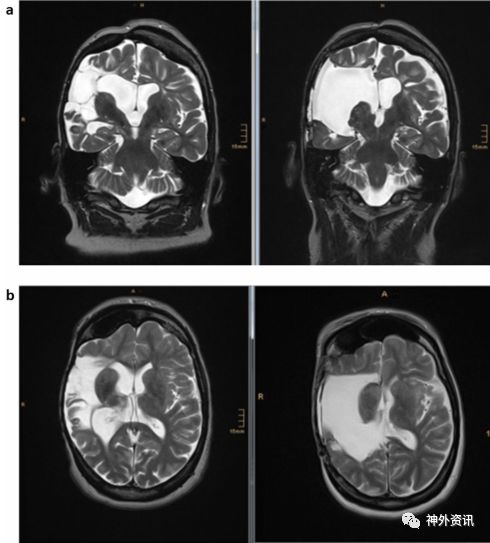

研究纳入1997年至2016年该中心行FH治疗的12例成人半脑病变合并难治性癫痫患者(图1),其中男性7例,女性5例;年龄在18-56岁之间,平均年龄34±12岁;癫痫首次发作时的平均年龄为4±4岁,癫痫病史平均30±12年;术后平均随访时间4.9年(表1)。收集患者术前的药物史、癫痫发作形式、神经系统检查和神经心理学评估等资料以及术后3个月和以后每年对患者的神经功能、认知功能和EEG的随访。

图1. a.FH术前 MRI-T2像;b.术后MRI-T2像。